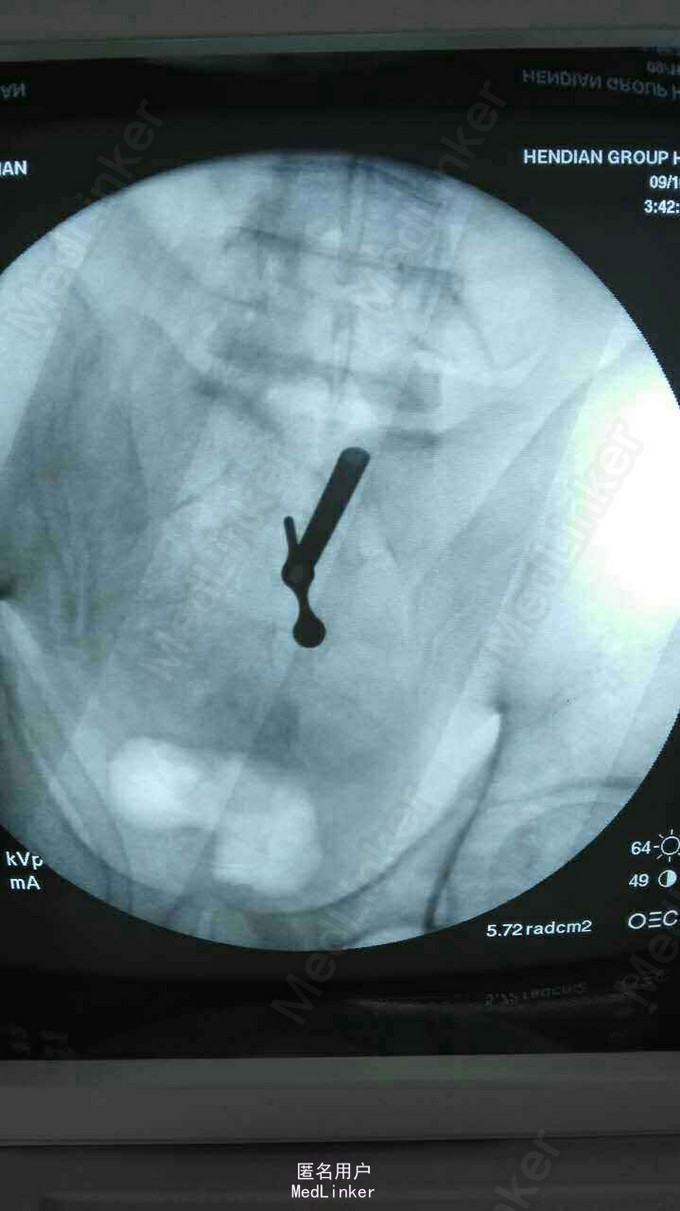

诊断:L5/S1椎间盘脱出(右侧) 治疗:因保守治疗效果不佳,准备行手术治疗。

请大家谈谈该患者的手术方案:开放融合内固定术?椎间盘镜手术?椎间孔镜手术?还是其他方案?